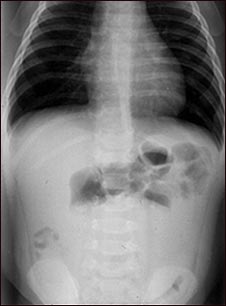

Radiografía de una invaginación

Esta radiografía abdominal muestra una condición en la que un asa intestinal se ha deslizado de otra sección del intestino (invaginación), causando hinchazón, reducción del flujo sanguíneo, obstrucción y daño a los tejidos. La invaginación requiere tratamiento de emergencia (enema de bario o cirugía) para evitar muerte del tejido intestinal (necrosis), perforación intestinal, peritonitis y la muerte del paciente.